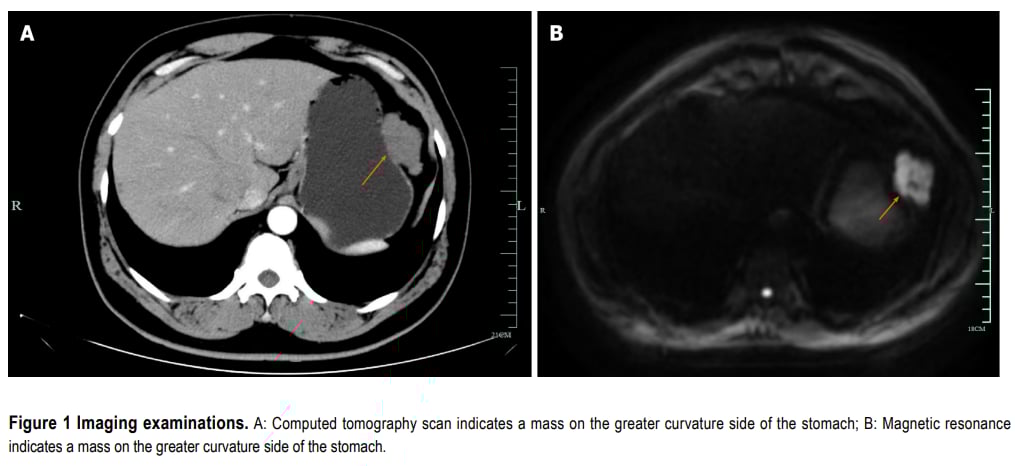

患者为47岁男性,因上腹部疼痛和可触及肿块就诊。影像学检查显示胃大弯处有一个大的外生性肿块,大小约5.0×6.0 cm。病理诊断为中等风险梭形细胞型GIST。免疫组化结果显示CD117(部分+)和DOG1(强+),但Ki-67增殖指数较低(约2%)。

▲图1 影像学结果(病例1腹部增强CT和MRI)